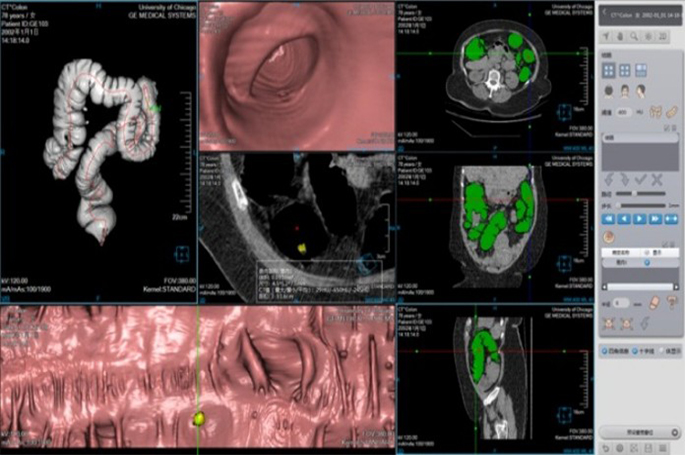

Cardiac Application Images

Coronary Calcium Scoring

Estimate the amount of calcium in the coronary arteries

• Agatston score

• Volume score

• ROI information calculation